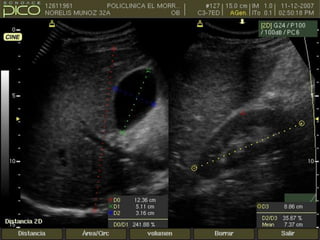

SOBREDISTENSION DE LA

VESICULA BILIAR

• AYUNO PROLONGADO

• OBSTRUCCION DE LA VESICULA

O DEL ARBOL BILIAR.

• VESICULA BILIAR NORMAL

OBSTRUCCION POR LITIASIS